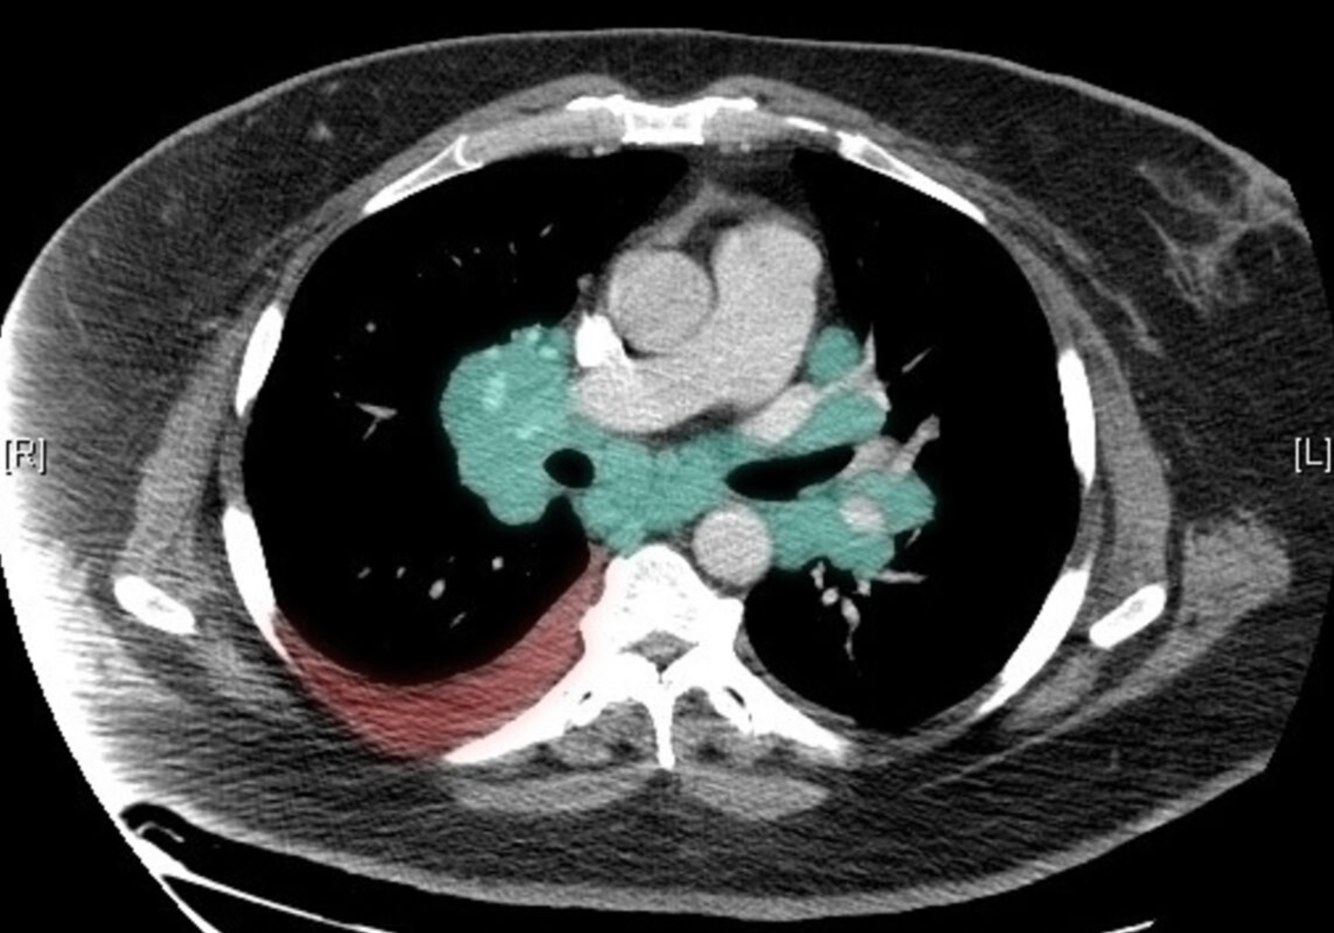

CT of the thorax (axial view)

Bilateral hyperdensities in the areas of the mediastinal and hilar lymph nodes can be seen (green overlay).

There is also evidence of right-sided pleural effusion (red overlay).

This is the typical appearance of bilateral lymphadenopathy, a common finding in sarcoidosis.